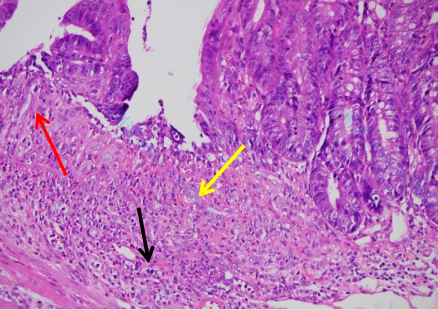

腸組織整體結構異常,組織可見較多粘膜上皮細胞潰瘍變性壞死,如圖黃色箭頭所示,組織壞死處可見少量纖維結締組織增生,如圖紅色箭頭所示,組織粘膜層杯狀細胞數量明顯減少,組織可見大量炎癥細胞浸潤,炎癥細胞累積組織全層,如圖黑色箭頭所示: